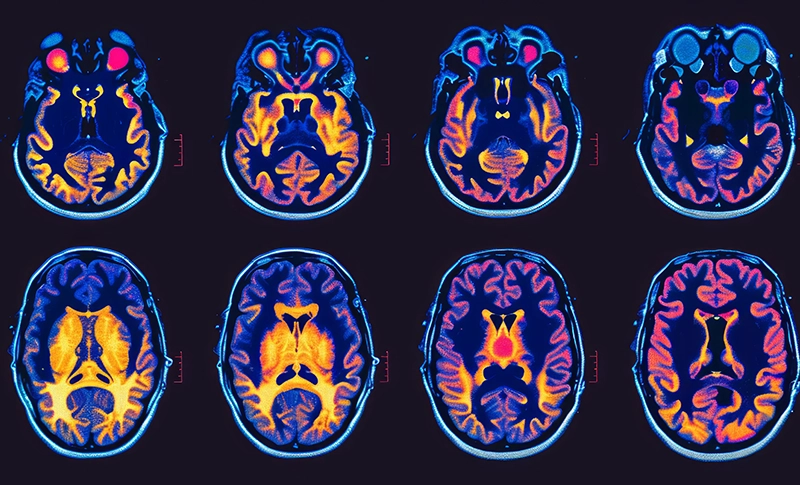

Learn about the unique challenges of the brain cancer experience, and gain valuable

insights and resources that can support patients and their families navigating this complex

and emotionally difficult disease. Read More ›

Molecular profiling is a critical step in the diagnosis and treatment of brain tumors. This advanced testing analyzes the genetic and molecular characteristics of a tumor to provide a deeper understanding of its behavior, guiding treatment decisions and potentially expanding options for care. Read More ›